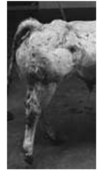

Quelle est la condition la plus probable chez cette génisse? a) Parésie spastique b) Syndrome spasmodique c) OCD du grasset d) Ulcère de sole e) Arthrite septique de l’articulation coxo-fémorale

**a) Parésie spastique** ## Footnote **La parésie spastique est un désordre neuromusculaire qui cause unehyperextension progressive unie ou bilatérale des jarrets et grassets.** Signes cliniques typiques => Jarret en extension =>Onglons soulevés =>Base de la queue surélevé ttt= anl reformé ou neverctomie